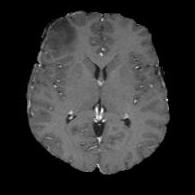

(a) (b) (c) (d) (e)

Comparison to Competing Methods:

We have compared the performance of our model against the most popular deep learning-based semantic segmentation networks, U-Net [9] and V-Net [7] (Fig. 3). Our model outperforms both by a considerable margin in all evaluation metrics. In particular, U-Net performs poorly in most cases due to the high false positive of its segmentation predictions, as well as the imprecision of its boundaries. The powerful residual block in the V-Net architecture seems to alleviate these issues to some extent, but V-Net also fails to produce high-quality boundary predictions. The emphasis of learning useful edge-related information during the training of our network appears to effectively regularize the network such that boundary accuracy is improved.